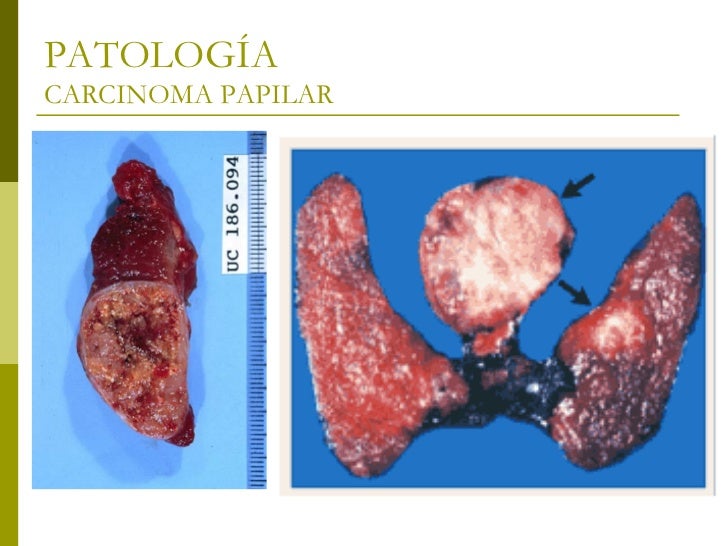

Carcinoma papilar de tiroides

V Congreso Virtual Hispanoamericano de Anatomía Patológica CARCINOMA